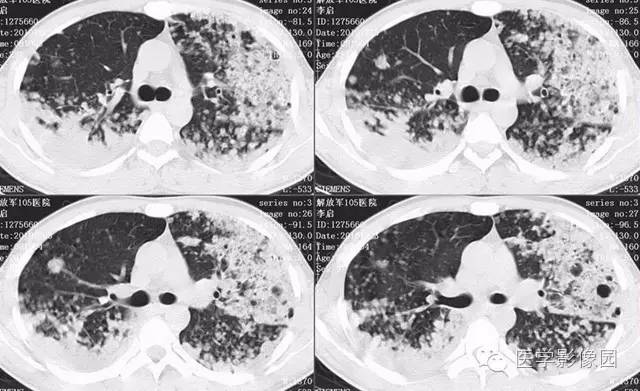

弥漫性肺泡细胞癌1例CT影像表现

病理结果:弥漫性肺泡细胞癌

弥漫性肺泡癌的主要临床及CT表现:临床表现无明显特征, 随着病情的进展, 咳嗽、 咳白痰、 进行性气促。CT表现 为病变分布有两种情况:病变累及一个肺段或肺叶;病变广泛分布于两肺。可归纳为5个特征性征象:蜂房征;支气管充气征;磨玻璃征;血管造影征;两肺弥漫分布的斑片状与结节影。